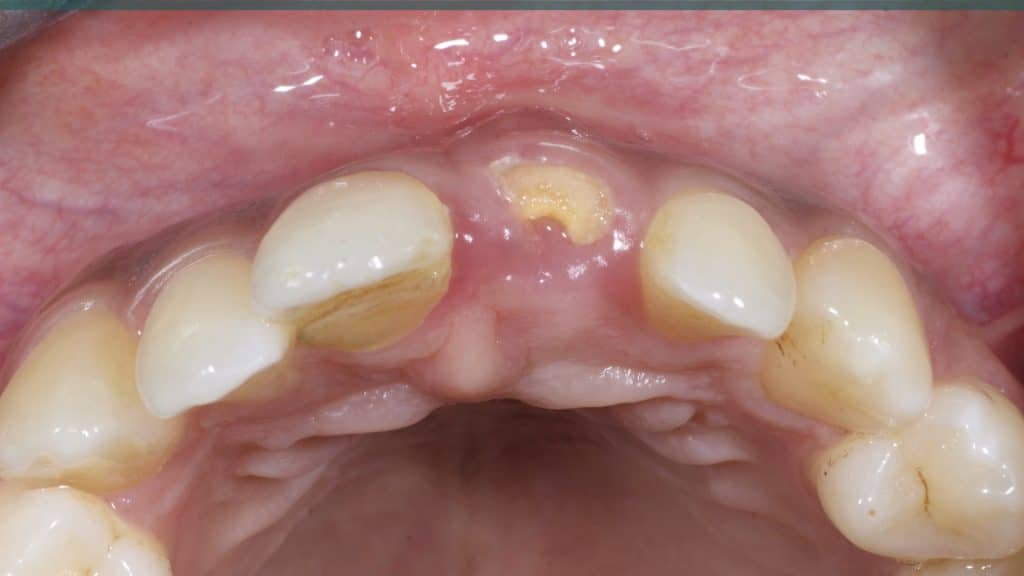

Occlusal check

20 days post-op after suture removal